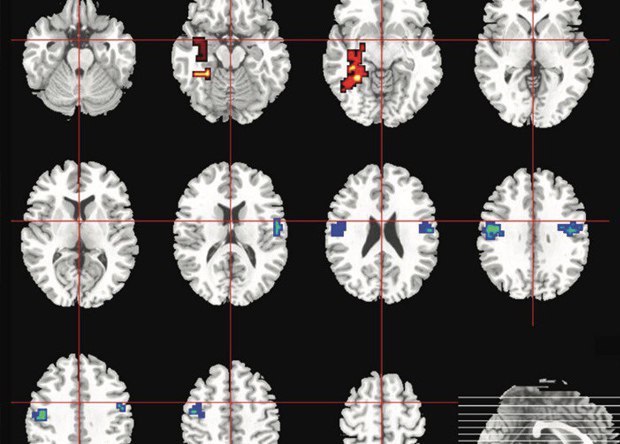

Потребление каннабиса не рекомендуется людям с повышенным риском развития психоза: его психоактивное вещество, тетрагидроканнабиноид, может негативно повлиять на работу участков мозга, отвечающих за когнитивные функции и эмоциональный контроль. При этом каннабиноид каннабидиол, наоборот, обладает антипсихотическими свойствами. Как выяснили американские ученые, у людей с повышенным риском развития психоза активность мозга после приема каннабидиола была больше похожа на «нормальную», чем в группе, которая принимала плацебо

http://short.nplus1.ru/cannabidiol